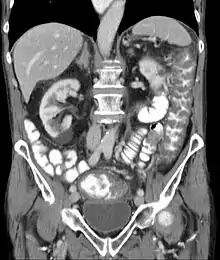

Pseudomembranous colitis on computed tomography

Prior to the advent of tests to detect C. difficile toxins, the diagnosis most often was made by colonoscopy or sigmoidoscopy. The appearance of "pseudomembranes" on the mucosa of the colon or rectum is highly suggestive, but not diagnostic of the condition.[42] The pseudomembranes are composed of an exudate made of inflammatory debris, white blood cells. Although colonoscopy and sigmoidoscopy are still employed, now stool testing for the presence of C. difficile toxins is frequently the first-line diagnostic approach. Usually, only two toxins are tested for—toxin A and toxin B—but the organism produces several others. This test is not 100% accurate, with a considerable false-negative rate even with repeat testing.[43]